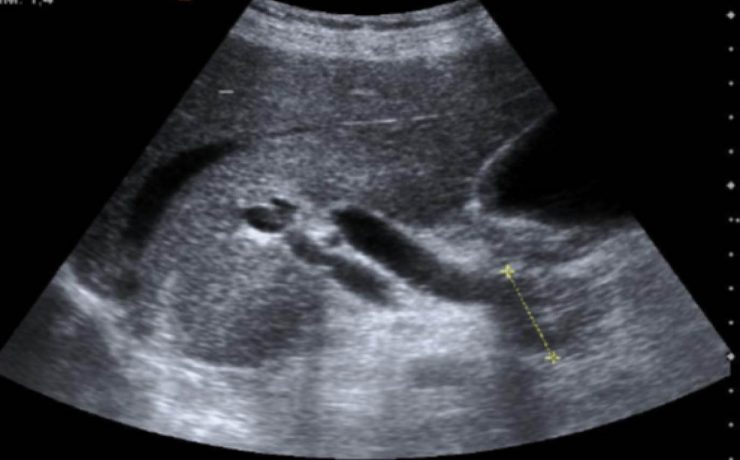

Se realizó un estudio descriptivo prospective, evaluando a 336 pacientes operados de colecistitis aguda o crónica por vía laparoscópica. Todos los pacientes fueron evaluados con ecografía abdominal al menos 7 días antes de la cirugía por un médico radiólogo experto y de acuerdo a varios parámetros se dividen en 3